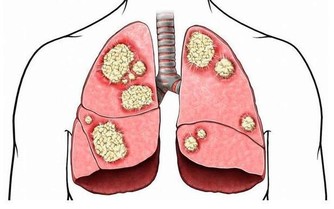

肺癌是中國發病率最高的癌症,也是死亡率最高的癌症。不管是何種癌症,我們都知道,一般發現時都是晚期,很難治愈。如果癌症早期能夠及時發現,經過治療後的五年生存率會大大提升。對於患者來說疾病的早發現要比“靈丹妙藥”見效好!